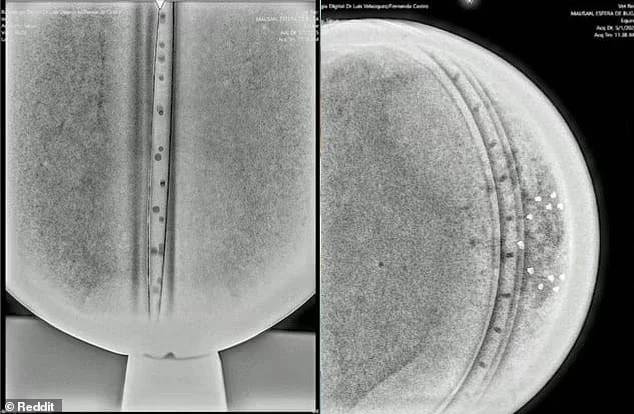

Phân tích X-quang cho thấy cấu trúc bên trong tinh vi, gồm 3 lớp kim loại, một “chip” trung tâm và 18 điểm nhỏ sắp xếp có chủ đích – điều không phổ biến trong công nghệ nhân loại.(Ảnh: Daily Mail)